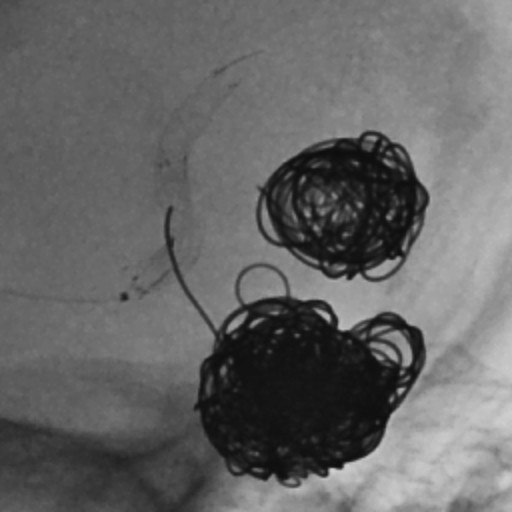

Endovaskularna terapija: Ova minimalno invazivna opcija uključuje umetanje katetera kroz krvne sudove radi zatvaranja aneurizme.